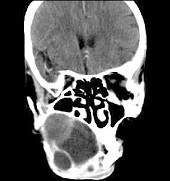

问题 男性,38岁,右侧下颌骨渐进性膨大半年,近来牙齿松动脱落,CT扫描如图所示,请选择最佳答案()

选项 A.动脉瘤样骨囊肿 B.造釉细胞瘤 C.骨软骨瘤 D.牙根囊肿 E.牙龈癌

答案 B